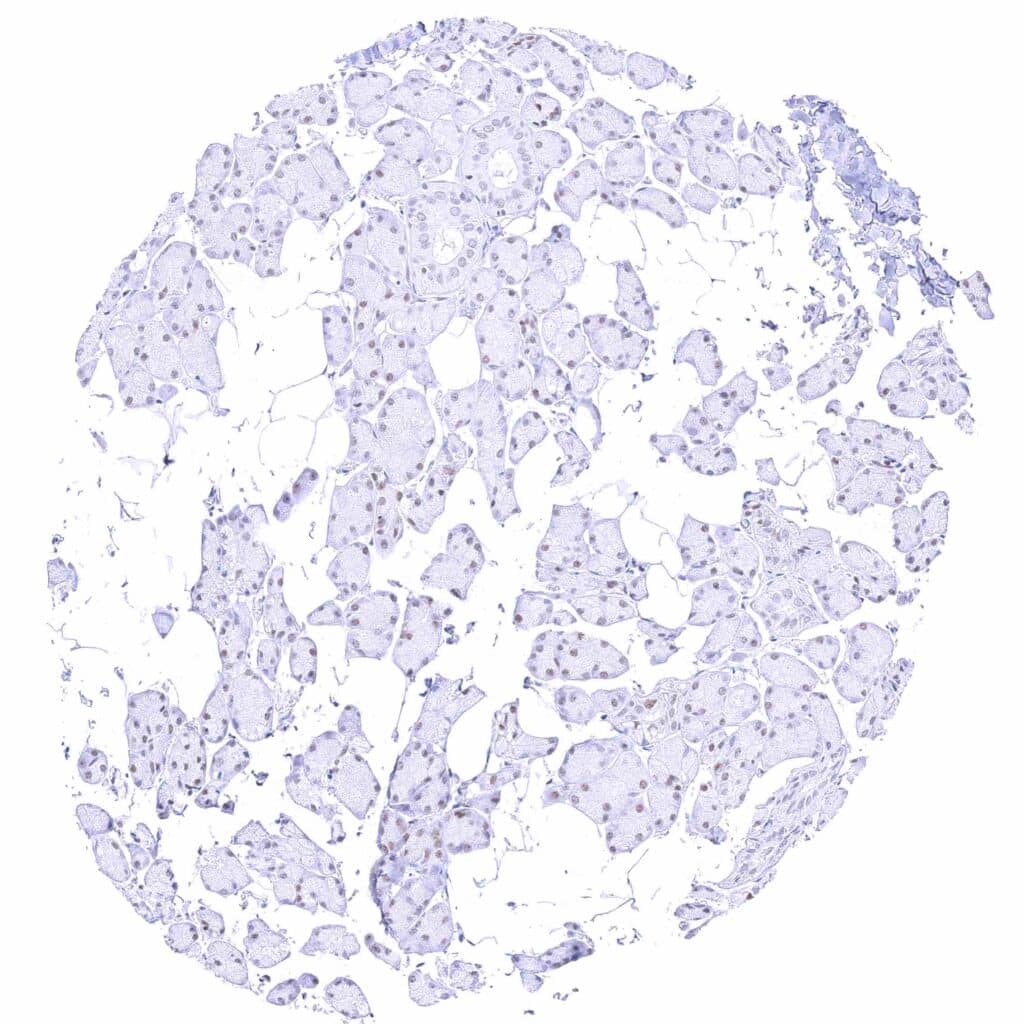

Placenta, early – Strong nuclear GATA3 positivity of trophoblastic cells.

Placenta, mature – Strong nuclear GATA3 positivity of trophoblastic cells.